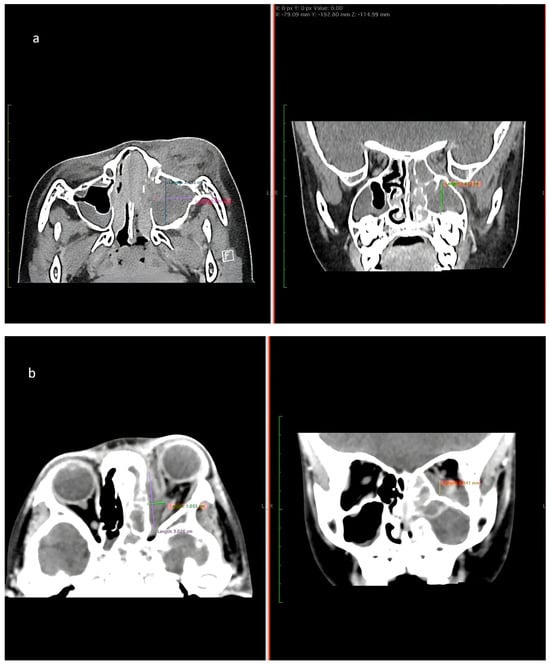

Figure 3. (a) CT of paranasal sinus shows intrasinus collection collectively measures approximately 2.5 cm × 2.0 cm × 1.9 cm (Anteroposterior × Width × Craniocaudal). (b) CT image shows rim-enhancing collection at the left subperiosteal region measuring 3.0 cm × 1.0 cm × 1.8 cm (Anteroposterior × Width × Craniocaudal).